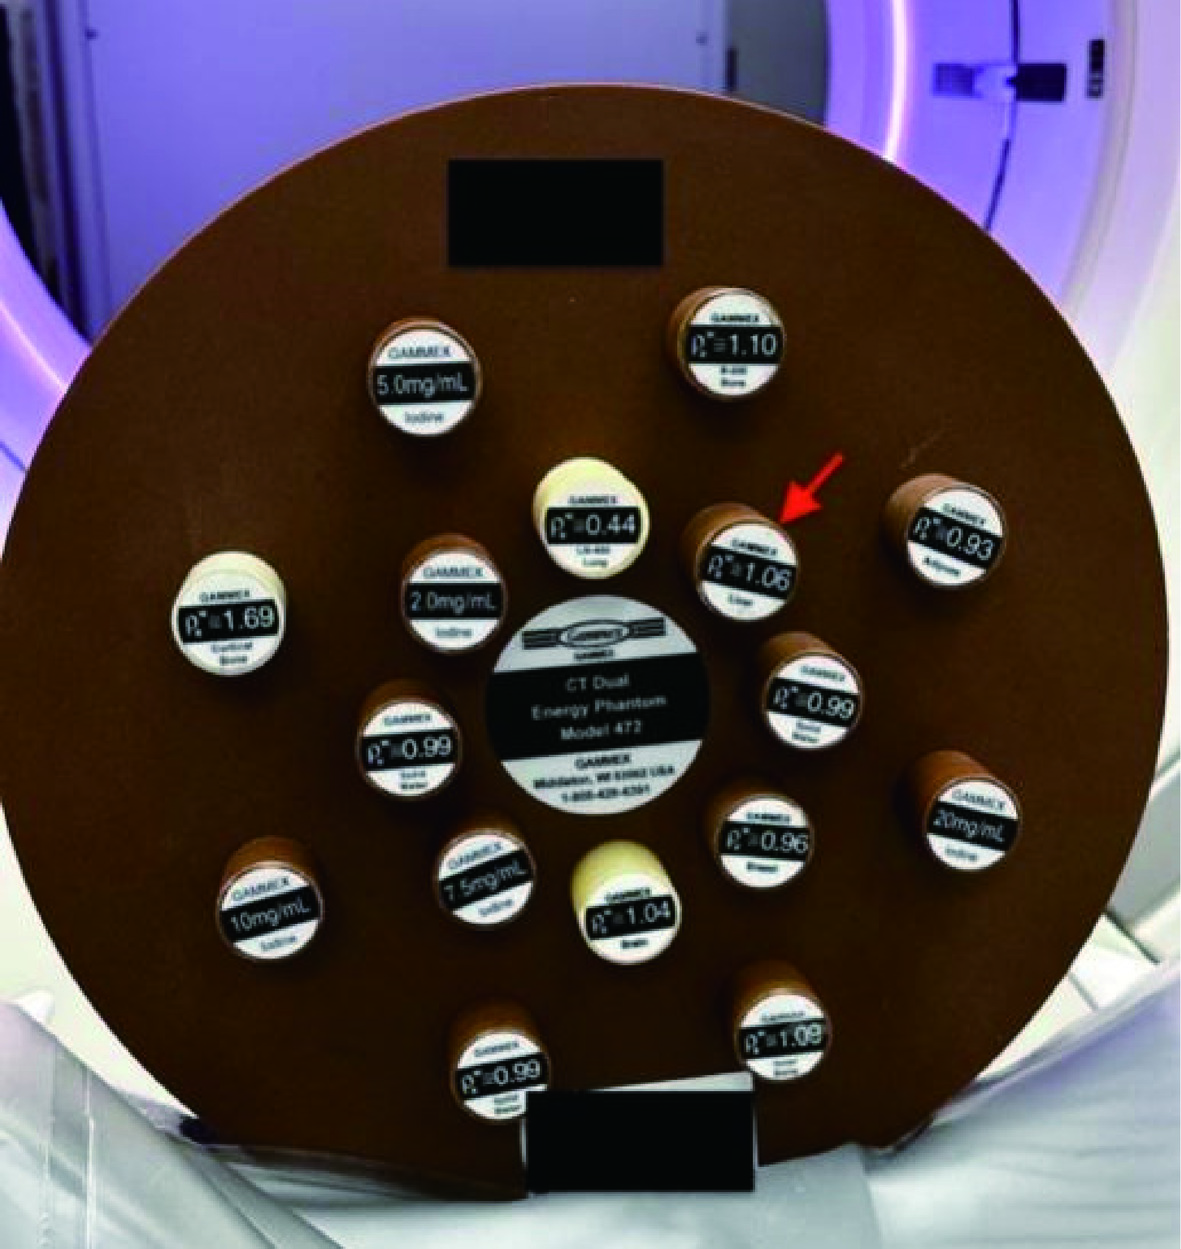

1.1 研究体模

本研究使用标准体模(Gammex CT phantom,model 472,Sun Nuclear)[14]。此体模设计为直径33 cm、层厚5 cm的圆盘形状,内含16个直径2.8 cm、长7 cm的插入物,用于模拟不同的人体组织密度。

在本实验中,我们特别测量了代表标准肝脏密度(ρew=1.06)的插入物(图1箭头指示)。在整个扫描过程中,体模的位置始终保持固定不变。

1.2 CT扫描和算法重建

使用一台256排CT(Revolution CT,GE医疗)完成体模扫描工作(图1)。在进行扫描时,参照腹部诊断CT扫描参数设置(表1),将管电压设定为120 kVp[15],并根据需要调整管电流,以产生6种不同的辐射剂量(容积CT剂量指数(volume CT dose index(CTDIvol):30、20、15、10、7.5和4.5 mGy)。其中,以15 mGy的剂量为标准的腹部扫描剂量[13]。重建图像的层厚和层距都是1.25 mm,重建图像视野为30 cm×30 cm,图像重建矩阵为512×512。